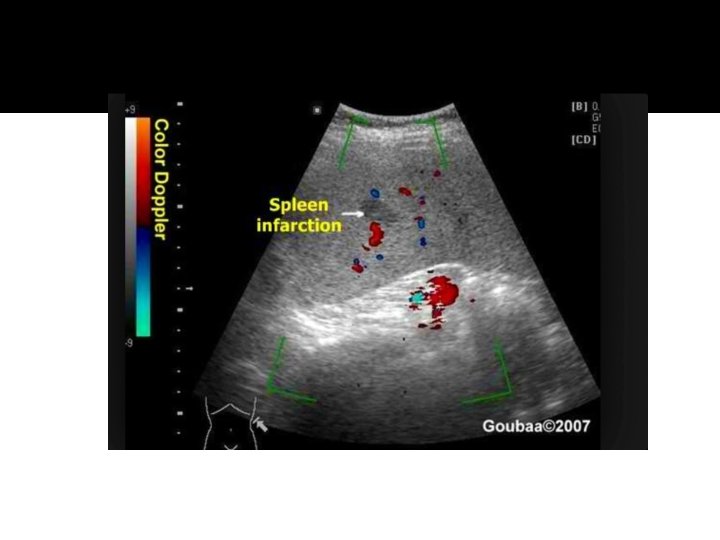

Splenic Infarcts �Infarcts: IV narcotic drug abuse leading to bacterial endodcarditis is a major cause of splenic infarction and its complication: Splenic abscess. �Embolic fragments from infected heart valves are carried in the bloodstream and lodge in the spleen causing an infarct which may heal or progress to an abscess. Infarcts may also be caused by leukemia and pancreatic cancer.

Splenic Infarct �Splenic infarcts are common in patients with bacterial endocarditis and splenic artery aneurysms. �They present as a peripheral wedge-shaped hypoechoic lesion. �The sonographic appearance of an infarct will change over time, as do hematomas. The initial ischemia and edema will appear as a hypoechoic wedge of tissue. With necrosis and liquification, the area will appear anechoic and ultimately will calcify.

Splenic infarcts �Sonographically, fresh infarcts are well defined, hypoechoic wedge-shaped focal lesions. The base of the wedge is towards the capsule and the apex towards the hilum. With time, the lesion shrinks and becomes more echogenic. �Complete healing may occur.

Splenic Infarct

Infarct

Wedge-Shaped Splenic Infarct